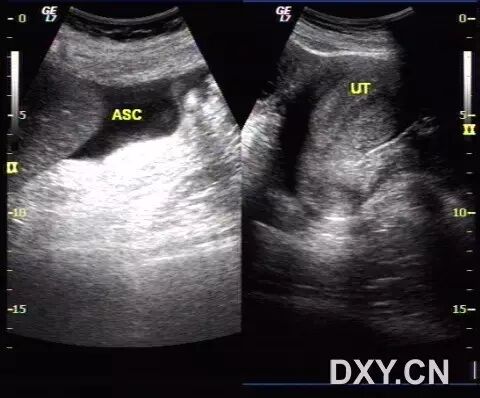

病例3(由丁香园注册用户「香水湾的传奇」提供):女性,26岁,因月经不调服用激素类药物治疗,现下腹痛来诊。

超声发现如下改变:

图1 显示肝脏周边的腹腔积液

图2 显示子宫内膜增厚且回声增强,呈分泌期改变

图3 显示双侧卵巢增大,其内可见多条分隔光带

图4 显示分隔内的丰富血流信号

图5 为治疗后超声改变,可见双侧卵巢体积缩小,卵泡数目减少,盆腔积液消失